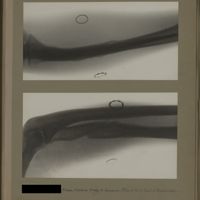

0123 - Page 11 - [Radiographies de l'épaule]0123 - Page 11 - [Radiographies de l'épaule]

0154 - Page 42 - [Radiographie de l'épaule]0154 - Page 42 - [Radiographie de l'épaule]

0170 - Page 58 - [Radiographie de l'épaule]0170 - Page 58 - [Radiographie de l'épaule]

0194 - Page 82 - [Radiographie de l'épaule]0194 - Page 82 - [Radiographie de l'épaule]